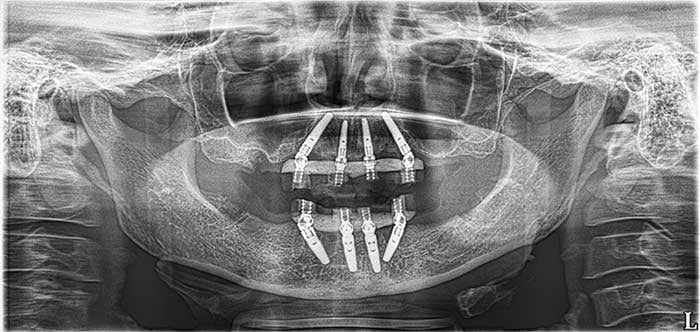

Our Work

Smile Gallery